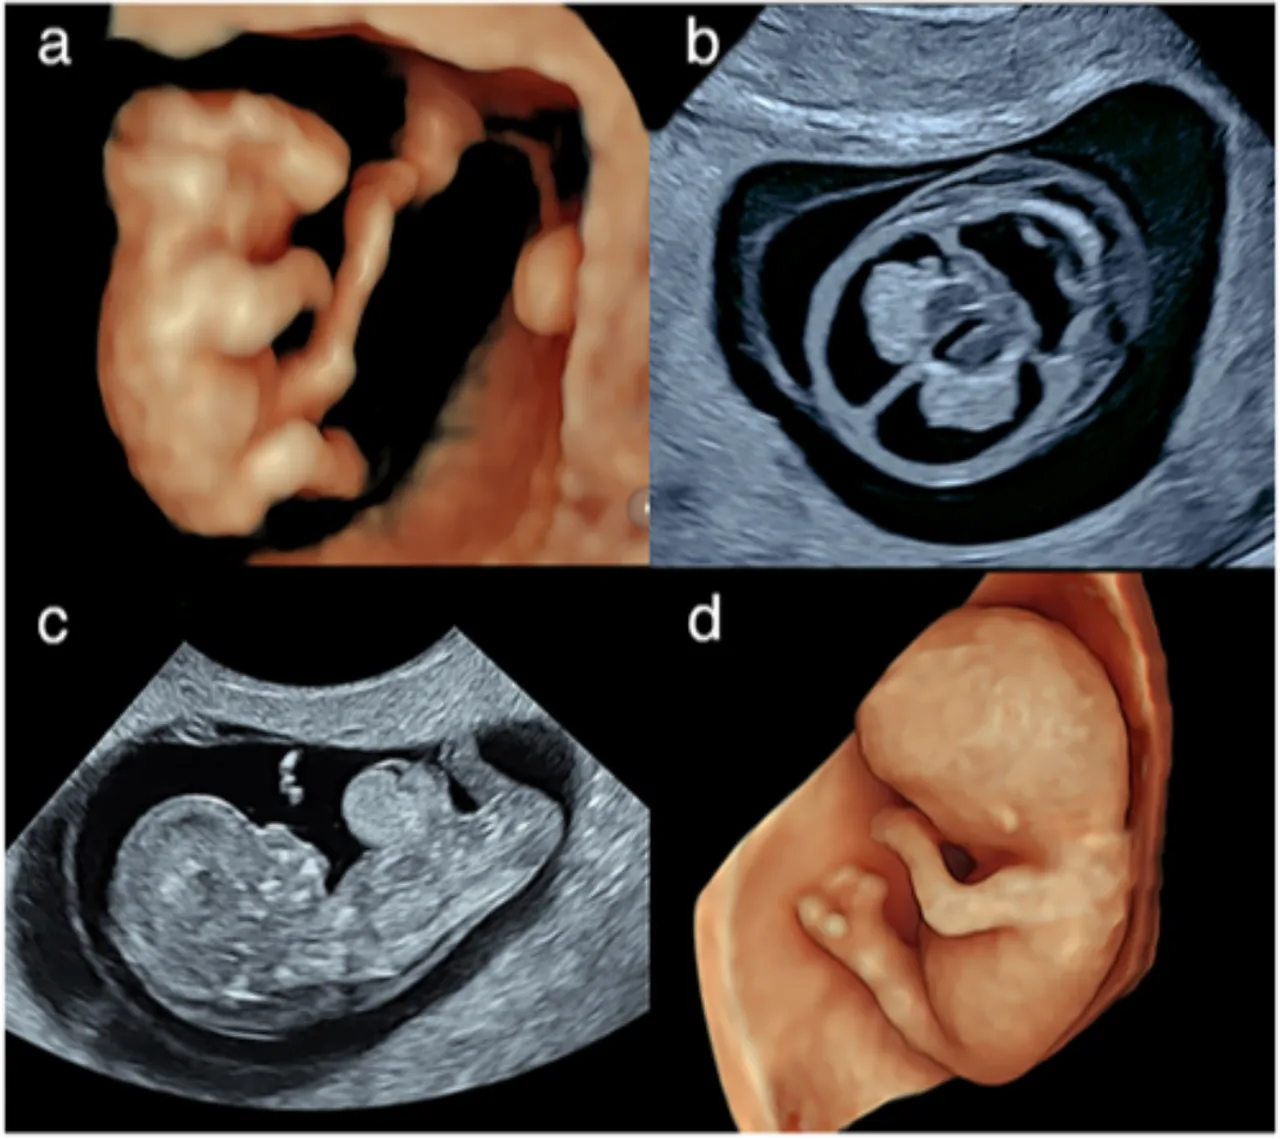

KADININ KANINDA FARKLI KROMOZOM YAPISI

Genetik testler sırasında bir kadının kanında erkeklere özgü kromozom yapısı saptandı. Ayrıntılı incelemeler, durumun anne karnında ikiz kardeşten kaynaklanan nadir bir “kimerizm” vakası olduğunu gösterdi. Kadın, herhangi bir sağlık sorunu yaşamadan doğum yaptı.